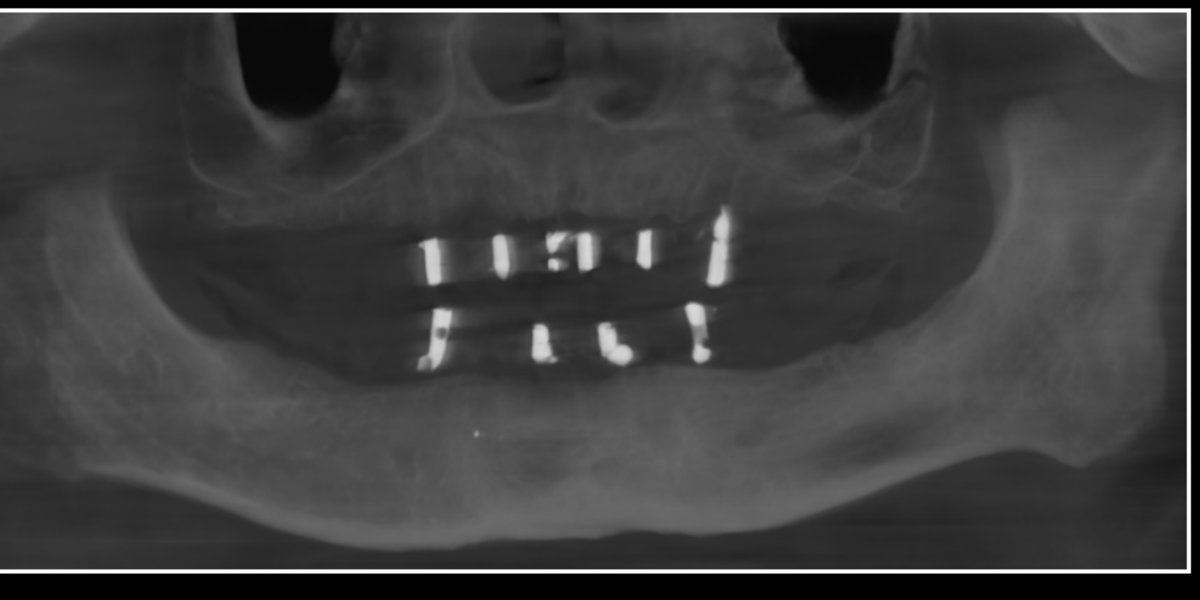

Dental Implants — OPG

Diagnostic radiograph case

OPG views showing precise implant placement and integration. Imaging-guided planning is at the core of every implant case here.